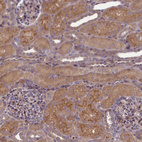

Immunohistochemical staining of human kidney shows strong cytoplasmic positivity in cells in tubules.